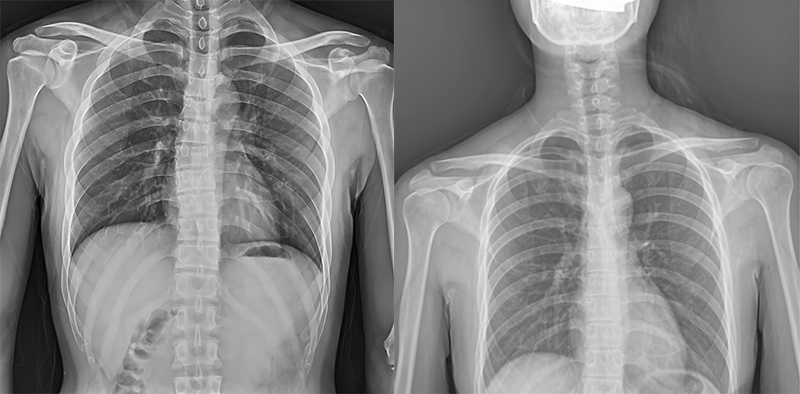

百微米DR與普通像素尺寸DR的影像對(duì)比

以胸部攝影為例,通過(guò)對(duì)比百微米大平板與普通像素尺寸平板的影像,可以看到百微米影像對(duì)比度適中,圖像清晰度更高,成像細(xì)節(jié)更加豐富。在胸部影像顯示中肺門(mén)影結(jié)構(gòu)、肺紋理等細(xì)節(jié)展示更清楚,兩側(cè)膈肌邊緣、心臟、縱隔邊緣清晰銳利顯示,在影像中都可以清晰地顯示胸部細(xì)微結(jié)構(gòu),滿(mǎn)足臨床診斷要求。